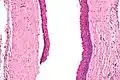

Micrograph of an odontogenic keratocyst. H&E stain.

Odontogenic keratocysts have a diagnostic histological appearance. Under the microscope, OKCs vaguely resemble keratinized squamous epithelium;[13] however, they lack rete ridges and often have an artifactual separation from their basement membrane.[2]

The fibrous wall of the cyst is usually thin and uninflamed. The epithelial lining is thin with even thickness and parakeratinised with columnar cells in the basal layer which have focal reverse polarisation (nuclei are on the opposite pole of the cell).[11] The basal cells are an indication of the odontogenic origin as they resemble pre-ameloblasts. The epithelium can separate from the wall, resulting in islands of epithelium. These can go on to form 'satellite' or 'daughter' cysts, leading to an overall multilocular cyst.[9] Presence of daughter cysts is particularly seen in those with NBCCS.[11] Inflamed cysts show hyperplastic epithelium which is no longer characteristic of OKCs and can have resemblance to radicular cysts instead. Due to areas of focal inflammation, a larger biopsy is required for correct diagnosis of odontogenic keratocysts.[9]